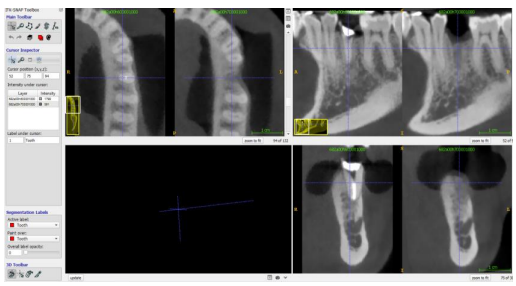

Patients were scanned using the Newtom VGI CBCT machine, with imaging conditions including 110 kv tube voltage, 2.2 to 8.30 mA tube current, 15 x 15 cm field of view, and 0.3mm voxel size. Projection data were collected with a device rotating 360 degrees around patients for 18 seconds. Images were evaluated using the NNT 5.6 software, which re-oriented the images according to three planes: horizontal, vertical, and mesio-distal. T1 and T2 DICOM images were imported and loaded simultaneously into the ITK-snap software, with T1 being the pre-operative CBCT and T2 four months post-operatively. The two CBCT scans were superimposed using the transform and general registration modules, and alignment was manually checked after registration in the three spatial planes. The software allowed a direct comparison of the two scans while maintaining the same alignment.

Figure 4 Screenshot of the ITK-Snap software showing the superimposition of the pre-op and post-op CBCT images in the 3 spatial planes.

3D volumetric measurements

The study involved volumetric measurements of pre and post-extraction sites, defined by their region of interest (ROI) in three dimensions: apically, mesio-distally, and buco-lingually. Three threshold-based semi-automatic active contour segmentations were performed: tooth segmentation, pre-operative alveolar socket segmentation, and post-operative alveolar bone segmentation. Each segmentation was manually rechecked to remove missing voxel selection. The volume of the T1 and T2 bone was measured using the volumes and statistics tool in the software. All clinical and radiographic measurements were performed by one operator and double checked by an experienced operator in oral and maxillofacial imaging. The duplicate measurements differed by <5%. The STL models were imported into 'Autodesk Netfabb', and a comparative analysis was carried out between the pre and post-operative models, resulting in color-coded figures to identify areas of resorption and bone gain. The results provide valuable insights into the procedure and its potential benefits.